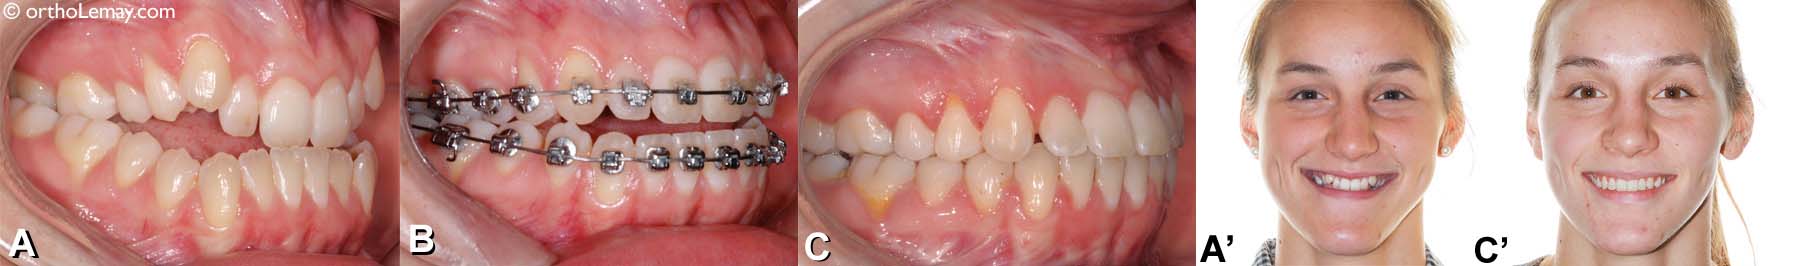

En plus de l’orthodontie ayant corrigé la position des dents, une chirurgie d’avancement du menton (génioplastie) a permis de changer le profil de cette adolescente de 18 ans. Photos : (A) Avant l’orthodontie, (B) après l’orthodontie et (C) après la génioplastie. – (Courtoisie : Dr Sylvain Chamberland, Québec)